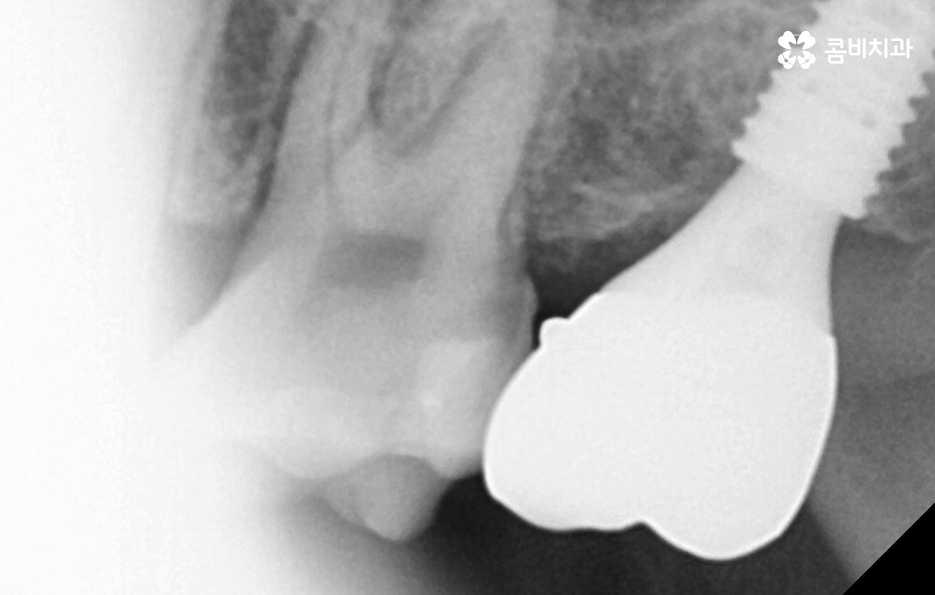

치아 발치 후에는 보통 약 2,3개월 정도 잇몸과 뼈가 차오르길 기다리며 그 이후에 잇몸 상태가 임플란트를 식립하기에 충분한 상태라면 임플란트를 잇몸 뼈에 식립하고 골유착과정을 약 3개월 정도 거친 후에 지대주를 세우고 보철물을 연결하여 치료를 마무리하고 있어요. 하지만 잇몸뼈 상태가 좋거나, 뼈이식과 동시에 진행하는 경우 발치 후 바로 식립을 진행하는 경우도 있어, 정확한 치료 계획은 의사와 상의를 해보시는 게 좋아요.

임플란트 치료가 끝나면 겉으로 보기에는 자연치아와 거의 유사한 심미성과 적응기간을 거치고 나면 저작력에 있어서 자연치아와 거의 유사한 정도의 저작기능을 수행하고 있는데요

어금니 발치후 임플란트 치료과정은 단계적으로 진행되고 일반적으로 임플란트 구조는 분리형이기 때문에 시술 후 관리 방법에 따라서 보철물의 이상 발생 시에는 사후관리를 통해 해결할 수 있지만 잇몸 뼈에 식립된 인공치근이 염증 등으로 인해 문제가 생기면 심각한 수명 문제로 이어질 수 있기 때문에 사후관리의 중요성이 무척이나 크며 치료만 잘 받는 것이 아니라 오랫동안 꾸준히 사후관리를 믿고 찾을 수 있는 치과를 잘 선택하실 필요가 있어요